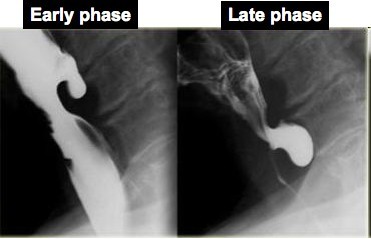

A 45 year old woman presents to her physician with increasing difficulty swallowing as well as trouble breathing at night. Upon barium swallow, the following is visible. What is her diagnosis and treatment?

Achalasia- esophageal dilation

Achalasia= Inability of the LES (lower esophageal sphincter) to relax after swallowing, resulting in periodic esophageal obstruction

Clinical: dysphagia, odynophagia, regurgitation, increased risk for squamous cell carcinoma

Histo: reduction/absence of myenteric ganglion cells

Barium swallow= see smoothly tapered distal end due to:

Diagnosis: barium swallow, upper endoscopy, abdominal CT, endoscopic ultrasound to rule out secondary causes (carcinoma, etc.)

Treatment: Botulinum toxin, pneumatic dilatation, surgical myotomy (laproscopic)